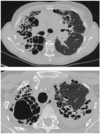

OAP interstitiel

Lymphangite carcinomateuse